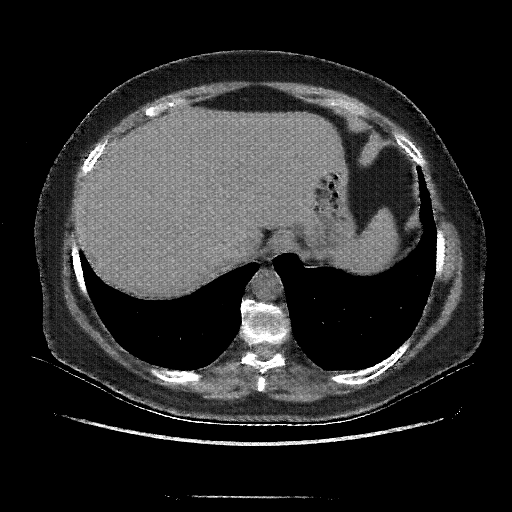

Image Grid

4Γ—3 grid: Rows show different image types (Original NATIVE, Reconstructed NATIVE, Original VENOUS, Generated VENOUS), Columns show windowing techniques (No Window, Lung Window, Mediastinum Window)

Original NATIVE CT scan (input)

Full window (WL 1023.5, WW 4095 β†’ Low βˆ’1024, High +3071)